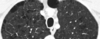

Enfisema

103

104

TC en enfisema

* Diagnóstica * Distingue distribución (centrolobulillar, panlobulillar o paraseptal) * Engrosamiento bronquial * Atrapamiento aire